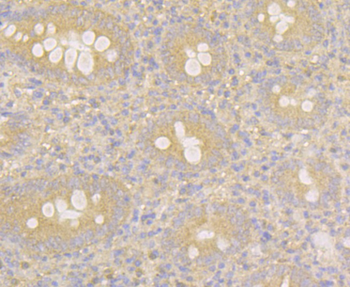

- PPM1D Rabbit Polyclonal Antibody [orb704535]Featured

IF, IHC-Fr, IHC-P

Human, Mouse, Rat

Mouse, Rat

Rabbit

Polyclonal

Unconjugated

100 μl, 50 μl, 200 μl - HSC70 Mouse Monoclonal Antibody [orb704174]Featured